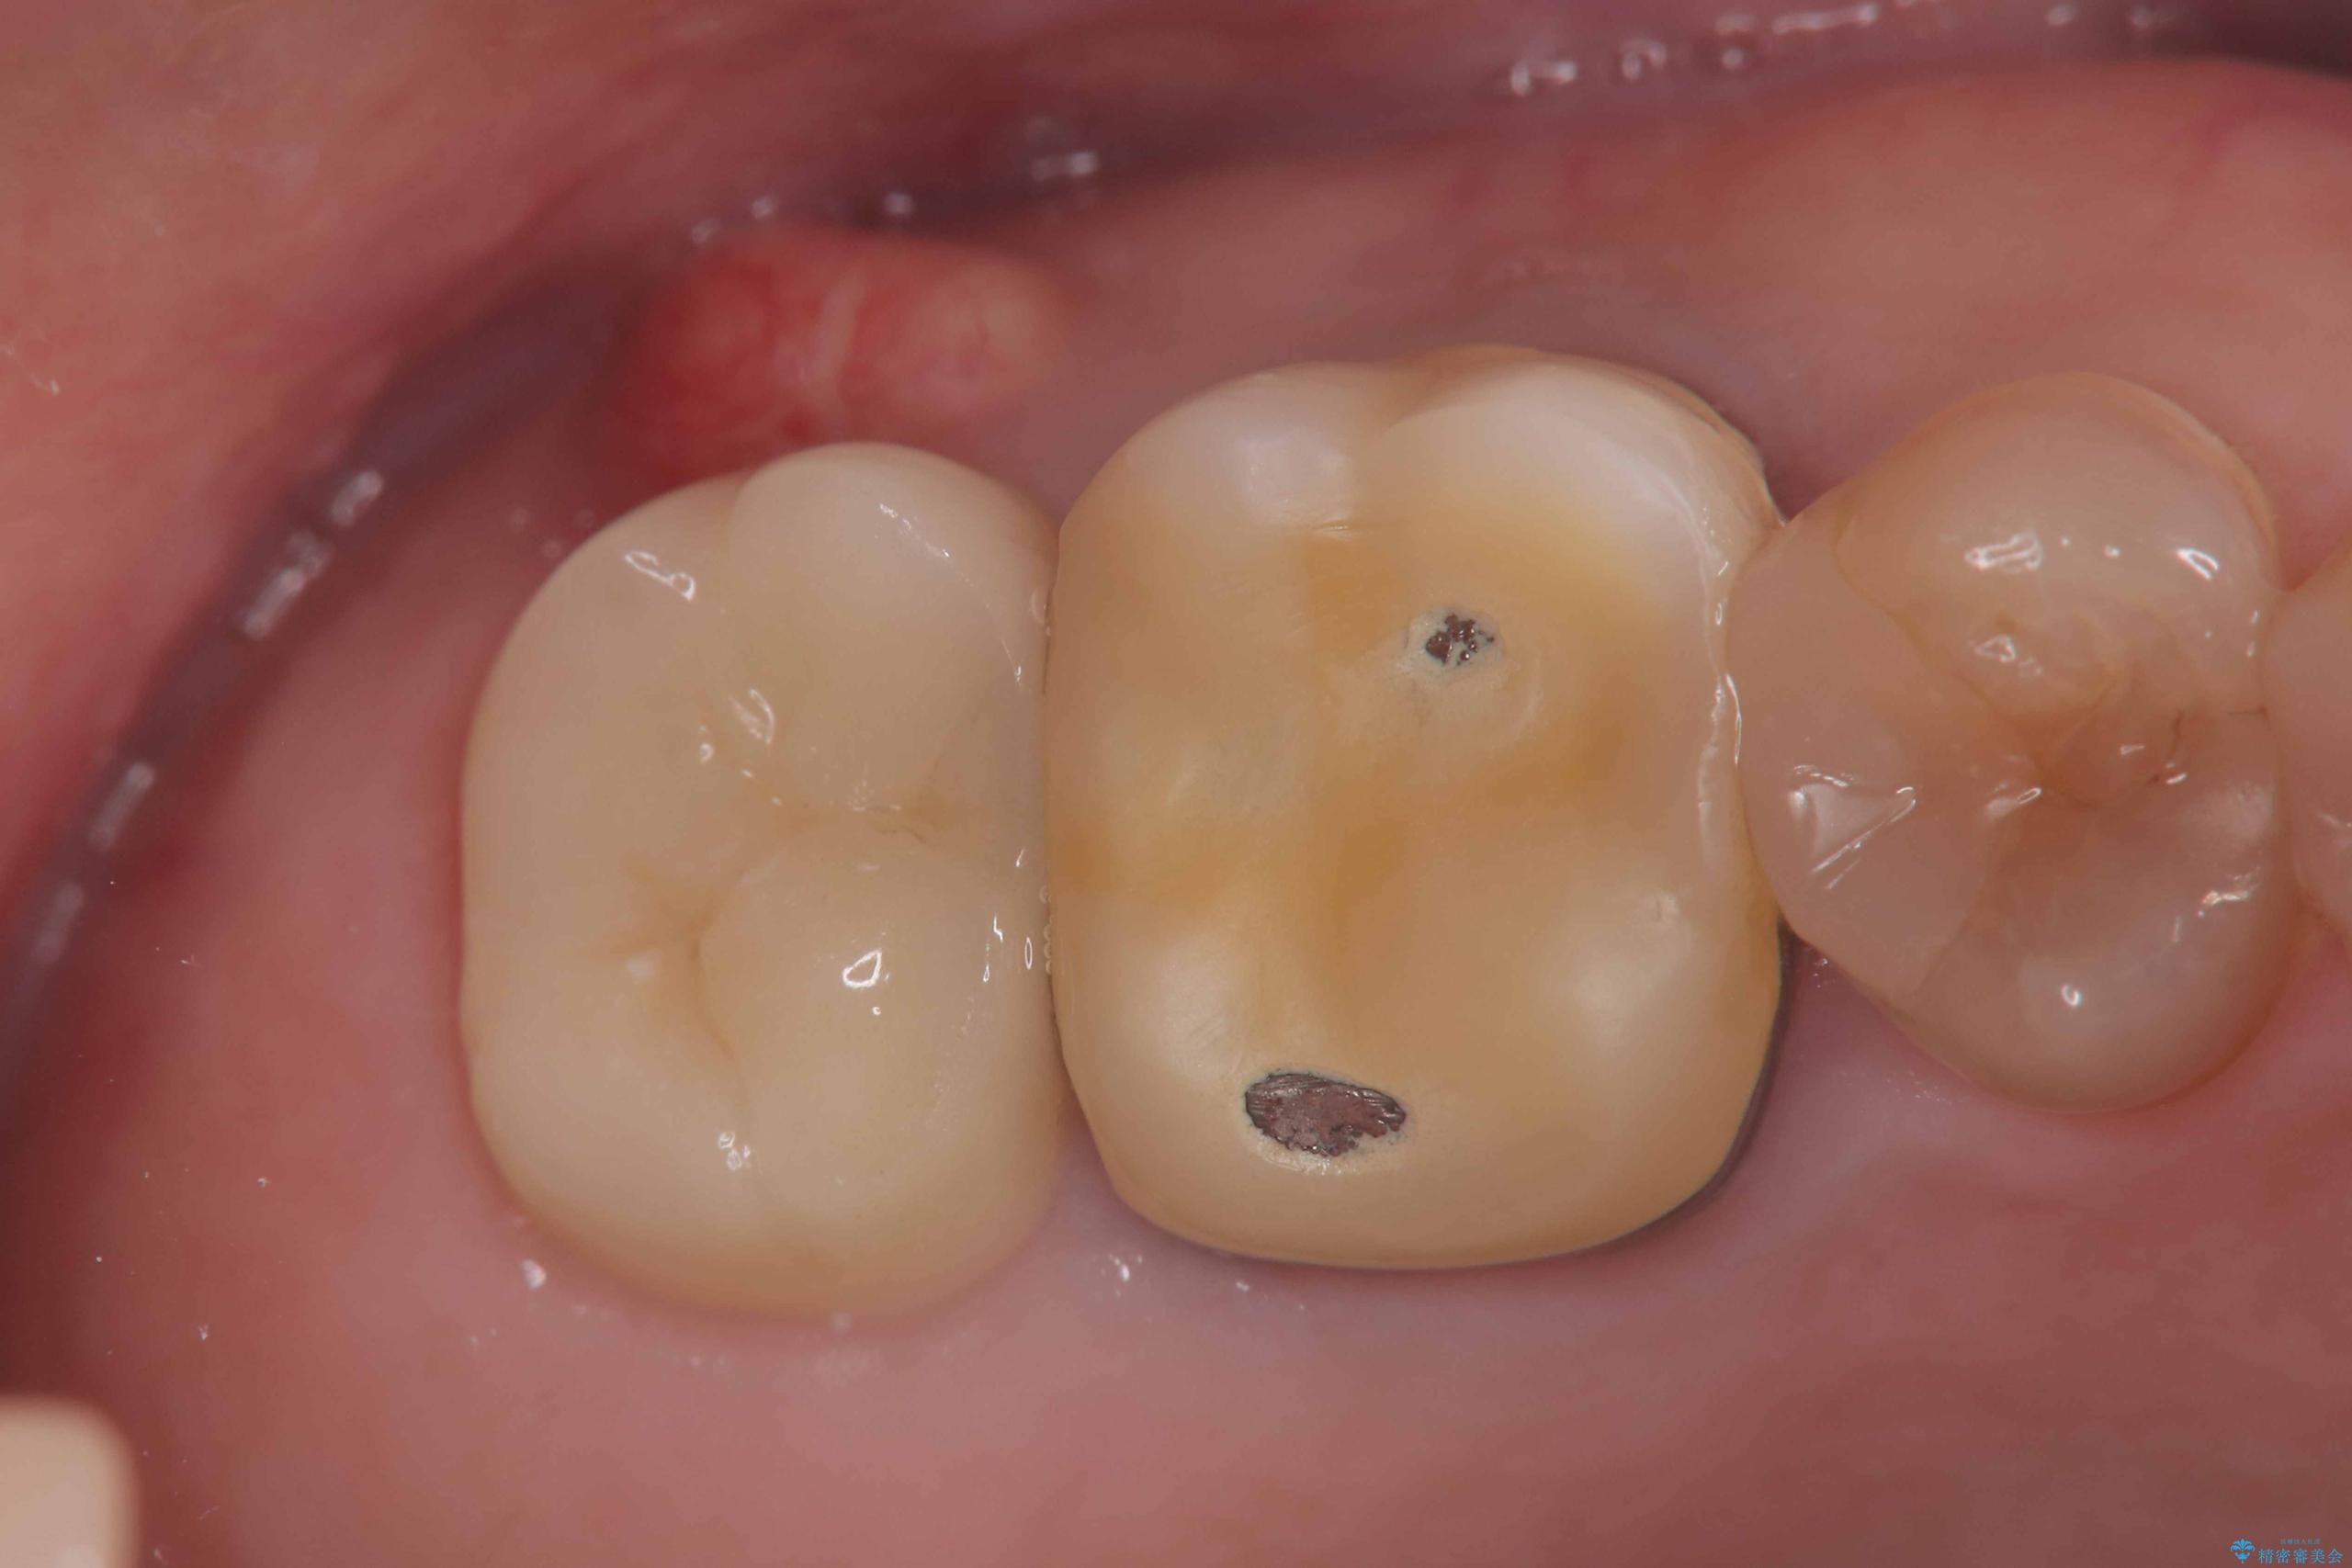

- 右上7番に瘻孔を認め、根管治療を実施しましたが、瘻孔が再発し治癒が得られなかったため、抜歯のうえインプラントによる補綴治療を行いました。

抜歯と歯根嚢胞の除去を行った後、インプラントで治療しました。治療後は「自分の歯のように咬める」と大変ご満足いただけました。